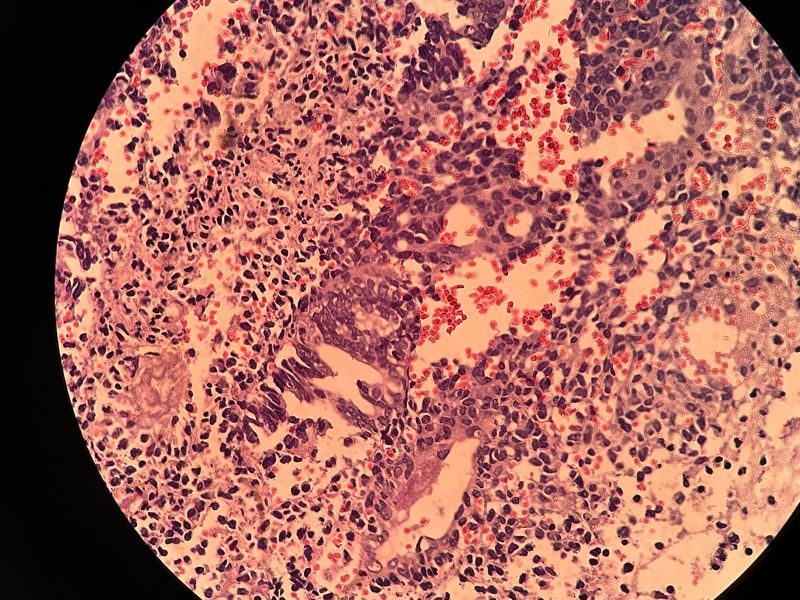

宫内膜组织

性别

女

年龄

37

临床诊断

功血

一般病史

阴道不规则流血20天

标本名称

大体所见

灰白灰红膜样物质一堆,约2.1✖️1.2✖️0.4

倾向内膜息肉

组织形态符合子宫内膜息肉,表面有乳头的那些区域要鉴别乳头样化生和表面浆液性肿瘤,免疫组化可能会有帮助。